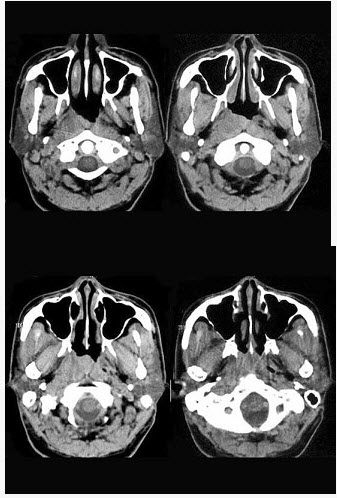

男,52岁,右耳鸣两月余,伴鼻塞,CT如图所示,应诊断为()。

A、鼻咽淋巴瘤

B、鼻咽纤维血管瘤

C、增殖体肥大

D、鼻咽癌

E、鼻咽部慢性炎症

D